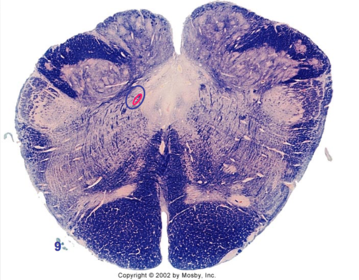

| Medullary pyramids | |

| Hypoglossal nucleus | |

| Hypoglossal nerve | |

| Dorsal motor nucleus of X | |

| Nucleus ambiguus | |

| Solitary tract | |

| Solitary nucleus | |

| ALS | |

| Medial lemniscus | |

| Medial longitudinal fasciculus | |

| Anterior spinocerebellar tract | |

| CN IX | |

| Inferior cerebellar peduncle | |

| Inferior olivary complex | |

| Dorsal cochlear nucleus | |

| Inferior vestibular nucleus | |

| Medial vestibular nucleus | |

| Spinal nucleus of V | |

| Spinal tract of V | |